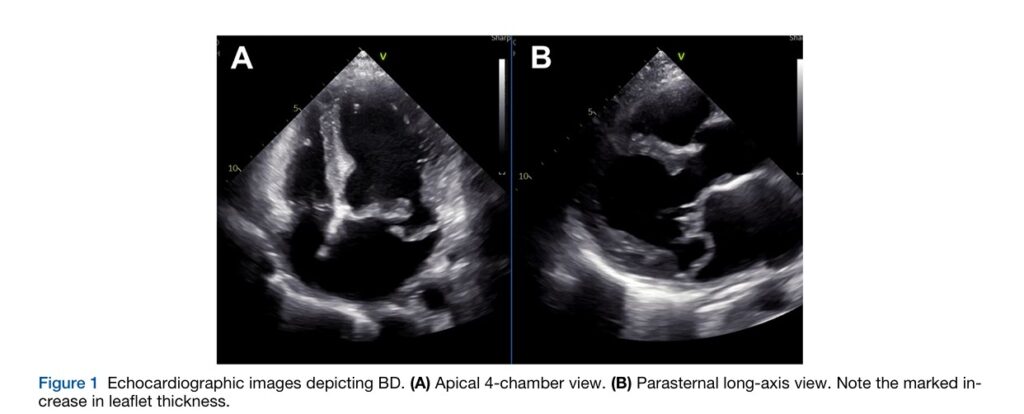

A doença de Barlow se caracteriza por folhetos alongados e espessados, acometendo também as cordoalhas tendíneas, com prolapso de ambos os folhetos e de vários segmentos.

A calcificação do anel mitral não é um achado incomum nos pacientes com PVM, especialmente naqueles com doença de Barlow. Na verdade, aproximadamente 1/4 dos pacientes com PVM submetidos a reparo cirúrgico demonstram esta alteração.